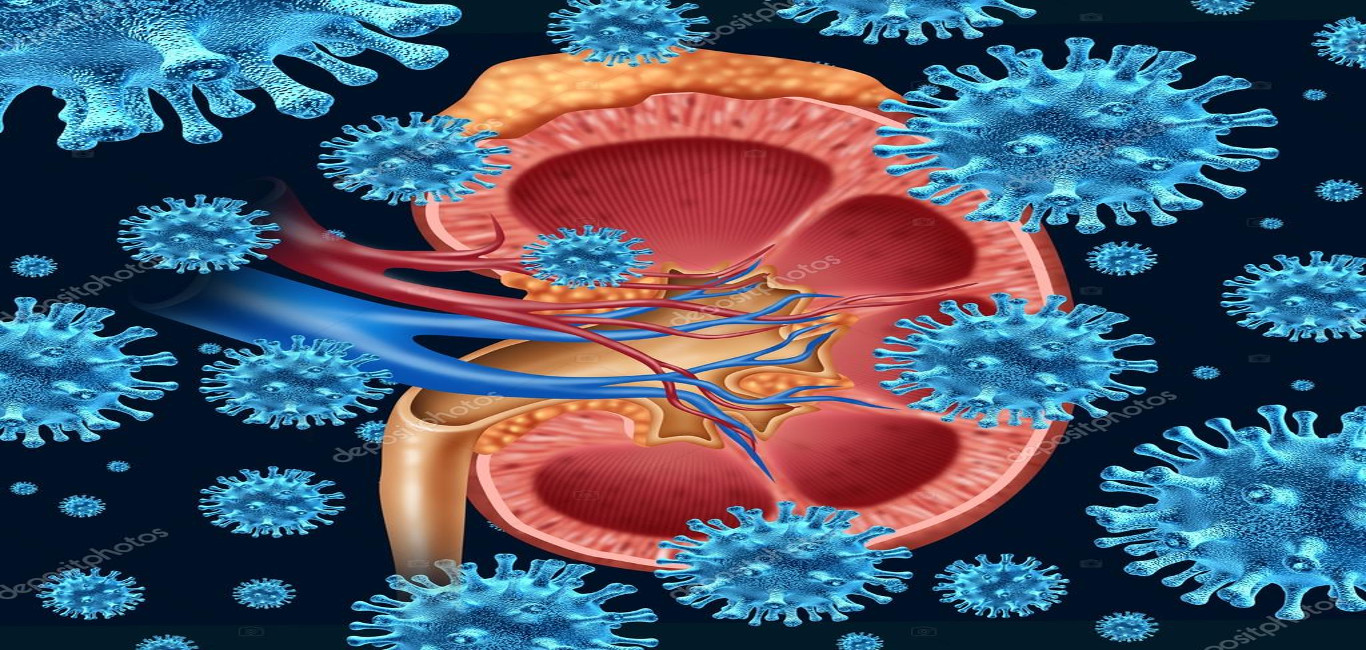

Κίνδυνοι από λοιμώξεις κατά την αιμοκάθαρση

Οι κεντρικοί φλεβικοί καθετήρες, που χρησιμοποιούνται ευρύτατα, ευθύνονται για το 90% των νοσοκομειακών λοιμώξεων (βακτηριαιμιών), από τις οποίες, στους ασθενείς υψηλού κινδύνου, το 10-20% έχουν θανατηφόρο έκβαση.

Αντίστοιχα οι κεντρικοί φλεβικοί καθετήρες αιμοκάθαρσης αποτελούν ακόμη και σήμερα σημαντικό μέσο για την αντιμετώπιση των ασθενών με τελικό στάδιο χρόνιας νεφρικής ανεπάρκειας (ΧΝΑ) με αιμοκάθαρση, η δε σήψη αποτελεί τη συχνότερη επιπλοκή εξ αιτίας της παρουσίας τους.